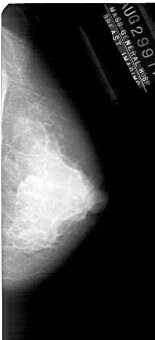

A_1927_1.RIGHT_MLO

RIGHT_MLO LINES 5491 PIXELS_PER_LINE 2476 BITS_PER_PIXEL 12 RESOLUTION 43.5 NON_OVERLAY